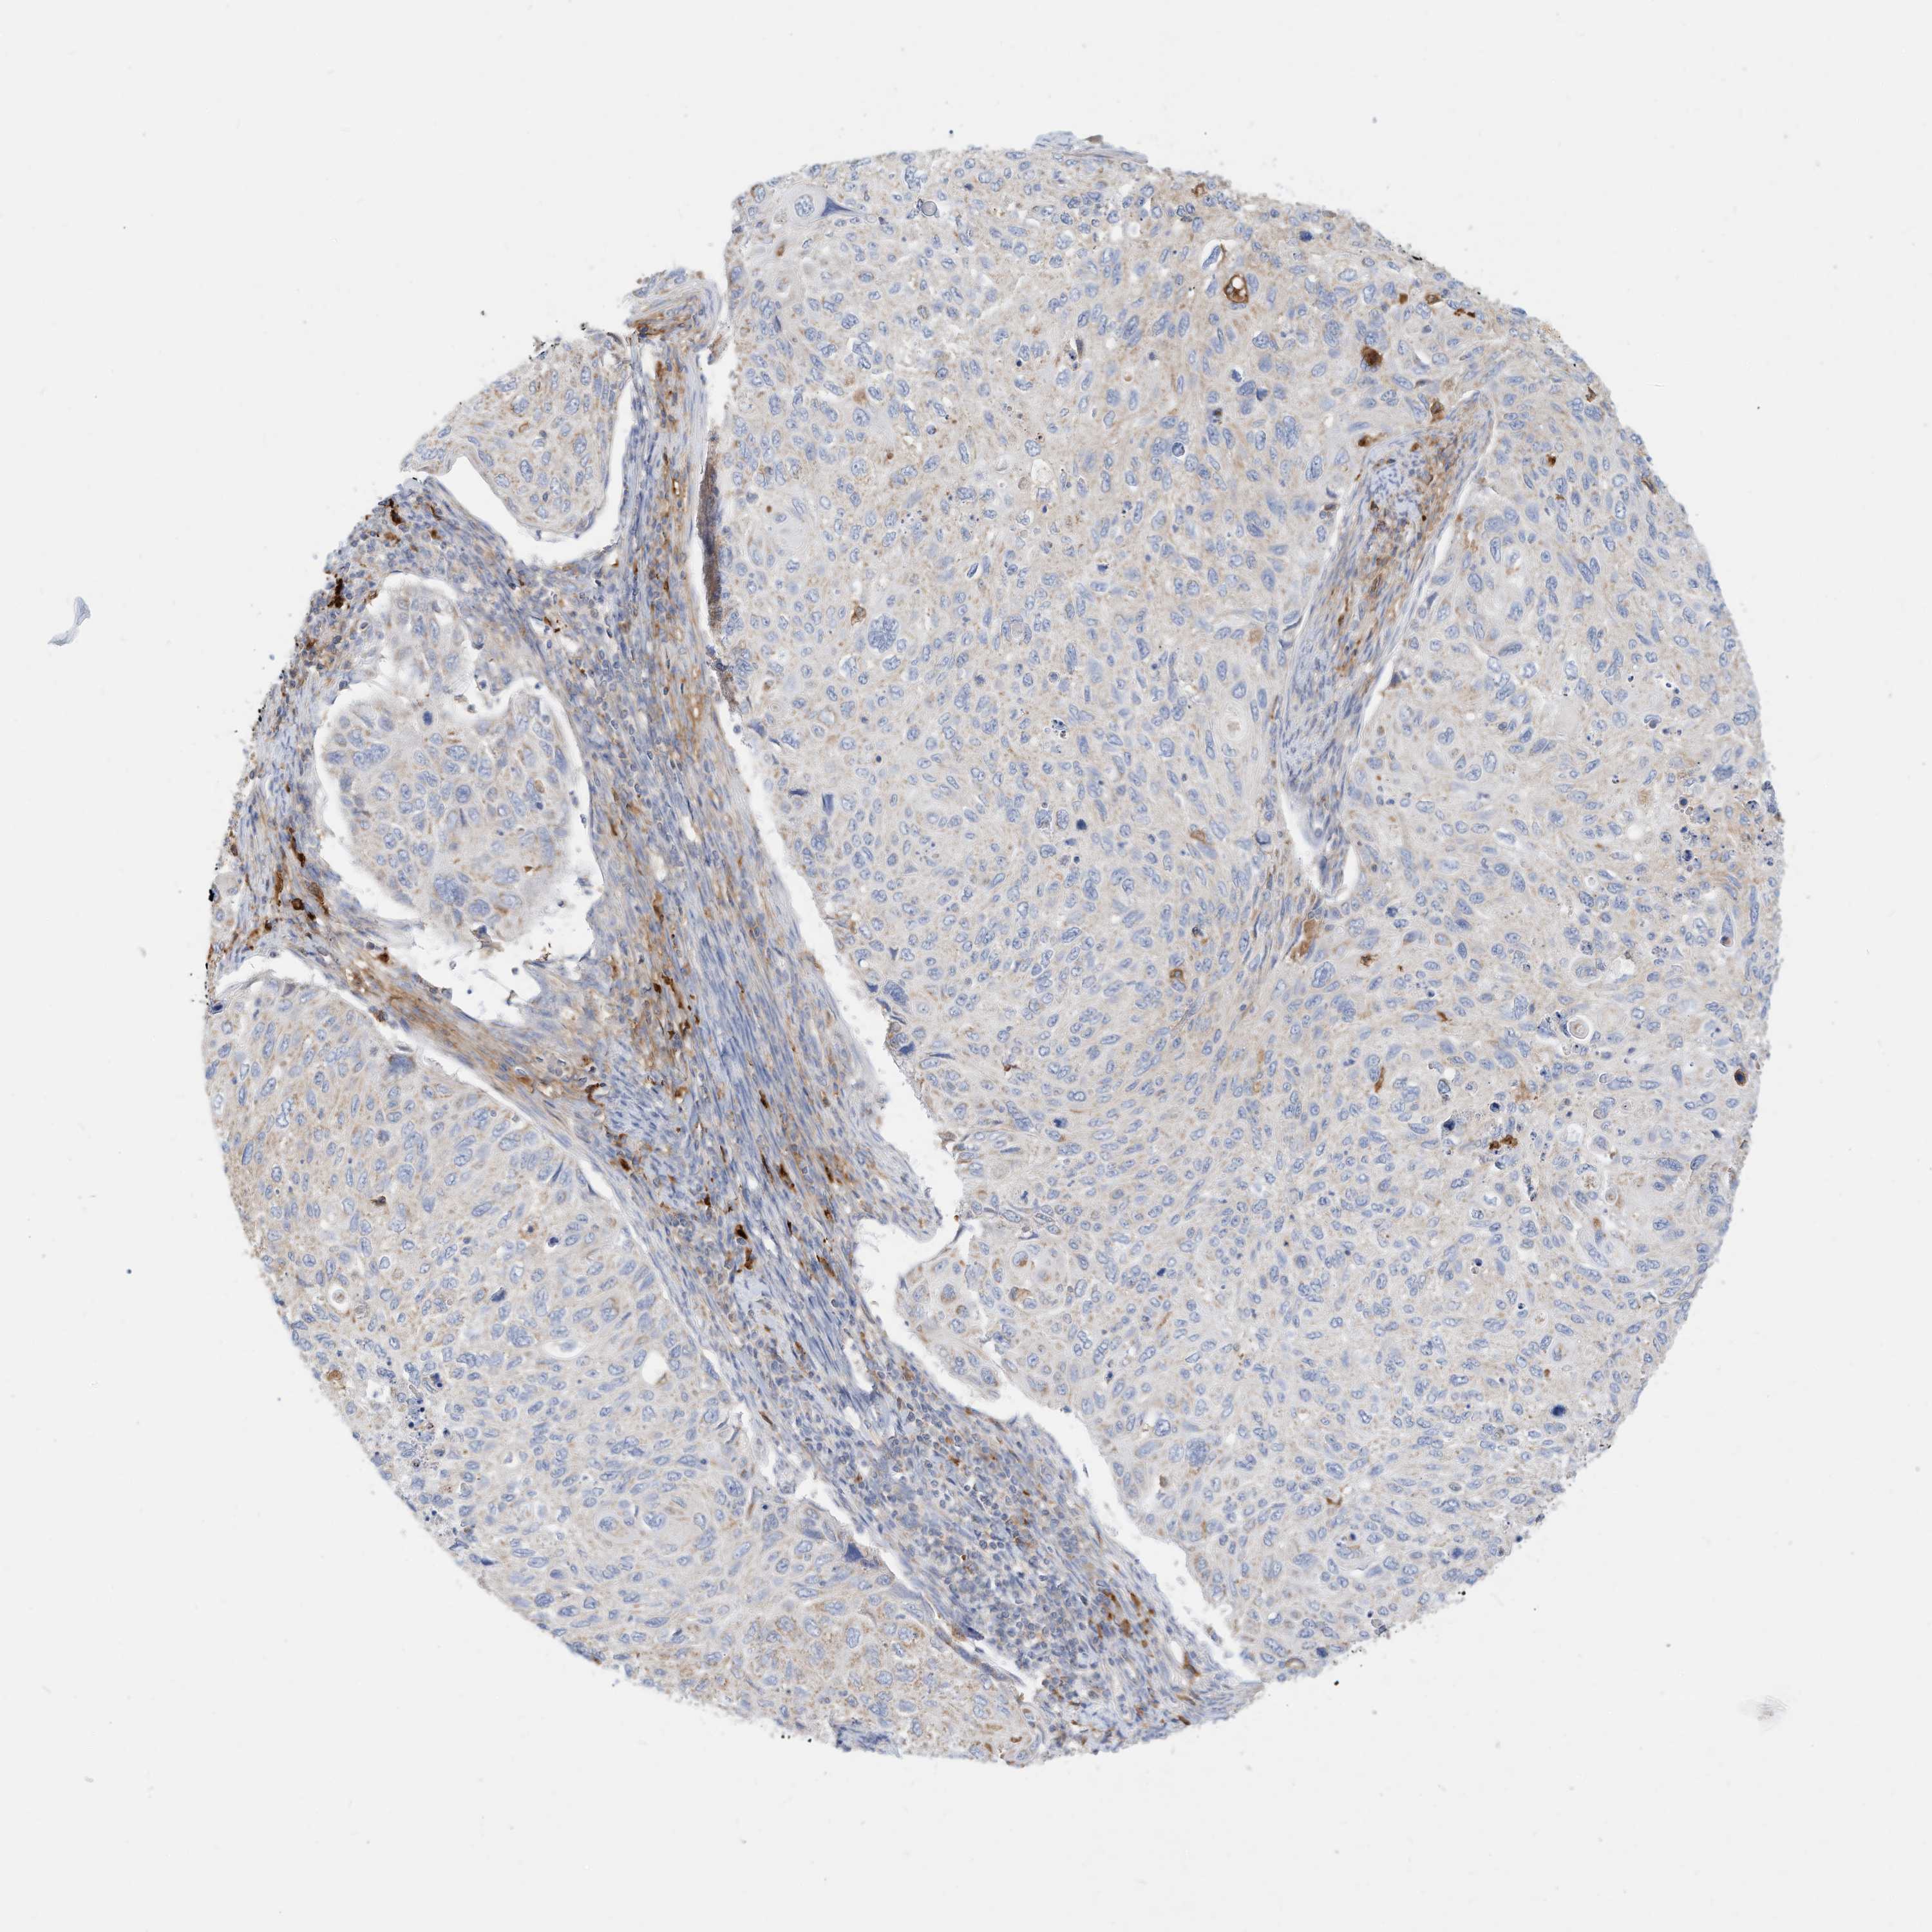

CERVICAL CANCER - Protein expressioni

A mouse-over function shows sample information and annotation data. Click on an image to view it in a full screen mode. Samples can be filtered based on level of antibody staining by selecting one or several of the following categories: high, medium, low and not detected. The assay and annotation is described here.

Note that samples used for immunohistochemistry by the Human Protein Atlas do not correspond to samples in the TCGA dataset.

Antibody stainingi

Antibody staining in the annotated cell types in the current human tissue is reported as not detected, low, medium, or high, based on conventional immunohistochemistry profiling in selected tissues. This score is based on the combination of the staining intensity and fraction of stained cells.

Each image is clickable and will lead to virtual microscopy that enables deeper exploration of all samples and also displays staining intensity scores, fraction scores and subcellular localization as well as patient and tissue information for each sample.

Antibody HPA030345

Squamous cell carcinoma, NOS

Adenocarcinoma, NOS